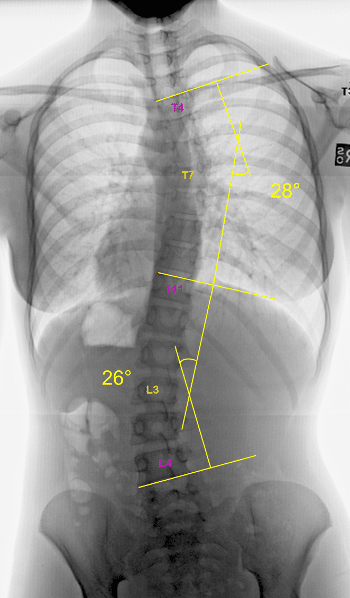

The Cobb angle is the most widely used measurement to assess the magnitude of spinal conditions, especially scoliosis, on an X-ray.

Accurate measurement of the Cobb angle is crucial for clinicians, and this measurement helps guide scoliosis treatment recommendations and management approaches.